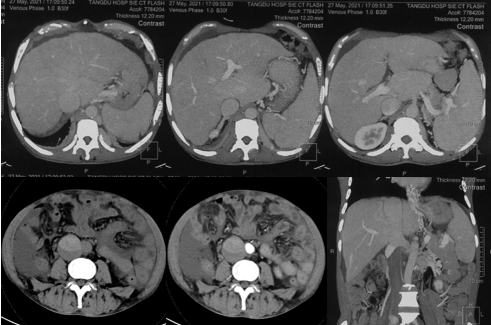

6月20日,患者及家屬懷揣著忐忑的心情來(lái)到西安國(guó)際醫(yī)學(xué)中心醫(yī)院找到韓國(guó)宏教授,韓教授詢問(wèn)病情后閱患者外院CT片,明確診斷布加綜合征,同時(shí)發(fā)現(xiàn)了一個(gè)新的問(wèn)題,在詢問(wèn)病史時(shí)了解到患者近一周雙下肢乏力伴腫脹明顯加重,遂立即安排了急診CT,證實(shí)下腔靜脈內(nèi)急性血栓形成!

6月22日,在韓國(guó)宏教授的帶領(lǐng)下,患者于消化介入診療中心行下腔靜脈開通術(shù)。術(shù)中可見:下腔靜脈全段擴(kuò)張,膜性閉塞,腎靜脈平面以下可見血栓形成并伴有粗大的側(cè)枝靜脈,遂對(duì)狹窄段球囊擴(kuò)張并植入支架,術(shù)后下腔靜脈血流通暢,側(cè)枝消失。術(shù)后第2天,患者腹壁靜脈曲張幾乎消失不見,走路也輕快了許多。明明只是薄薄的一層膜,為什么開通起來(lái)這么難?韓教授指出,盡管布加綜合征介入開通技術(shù)已使創(chuàng)傷降到了最低,但受到患者個(gè)體差異及醫(yī)療水平參差不齊的限制,仍有可能出現(xiàn)嚴(yán)重的并發(fā)癥,主要包括:心包積血、縱隔血腫、心包填塞甚至下腔靜脈撕裂引起的大出血等。而其發(fā)生率與術(shù)者的操作熟練程度及經(jīng)驗(yàn)有很大的關(guān)系。